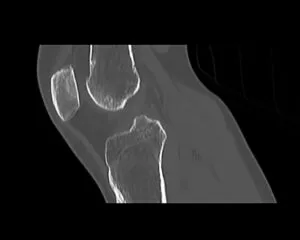

CT

GE社製Revolution ACT(16列)を導入しています。X線を利用して体の断面(輪切り)を撮像する検査です。この輪切りの画像をコンピューターで処理することにより、様々な方向からの断面像や3D画像を得ることができます。

CTで検査した画像